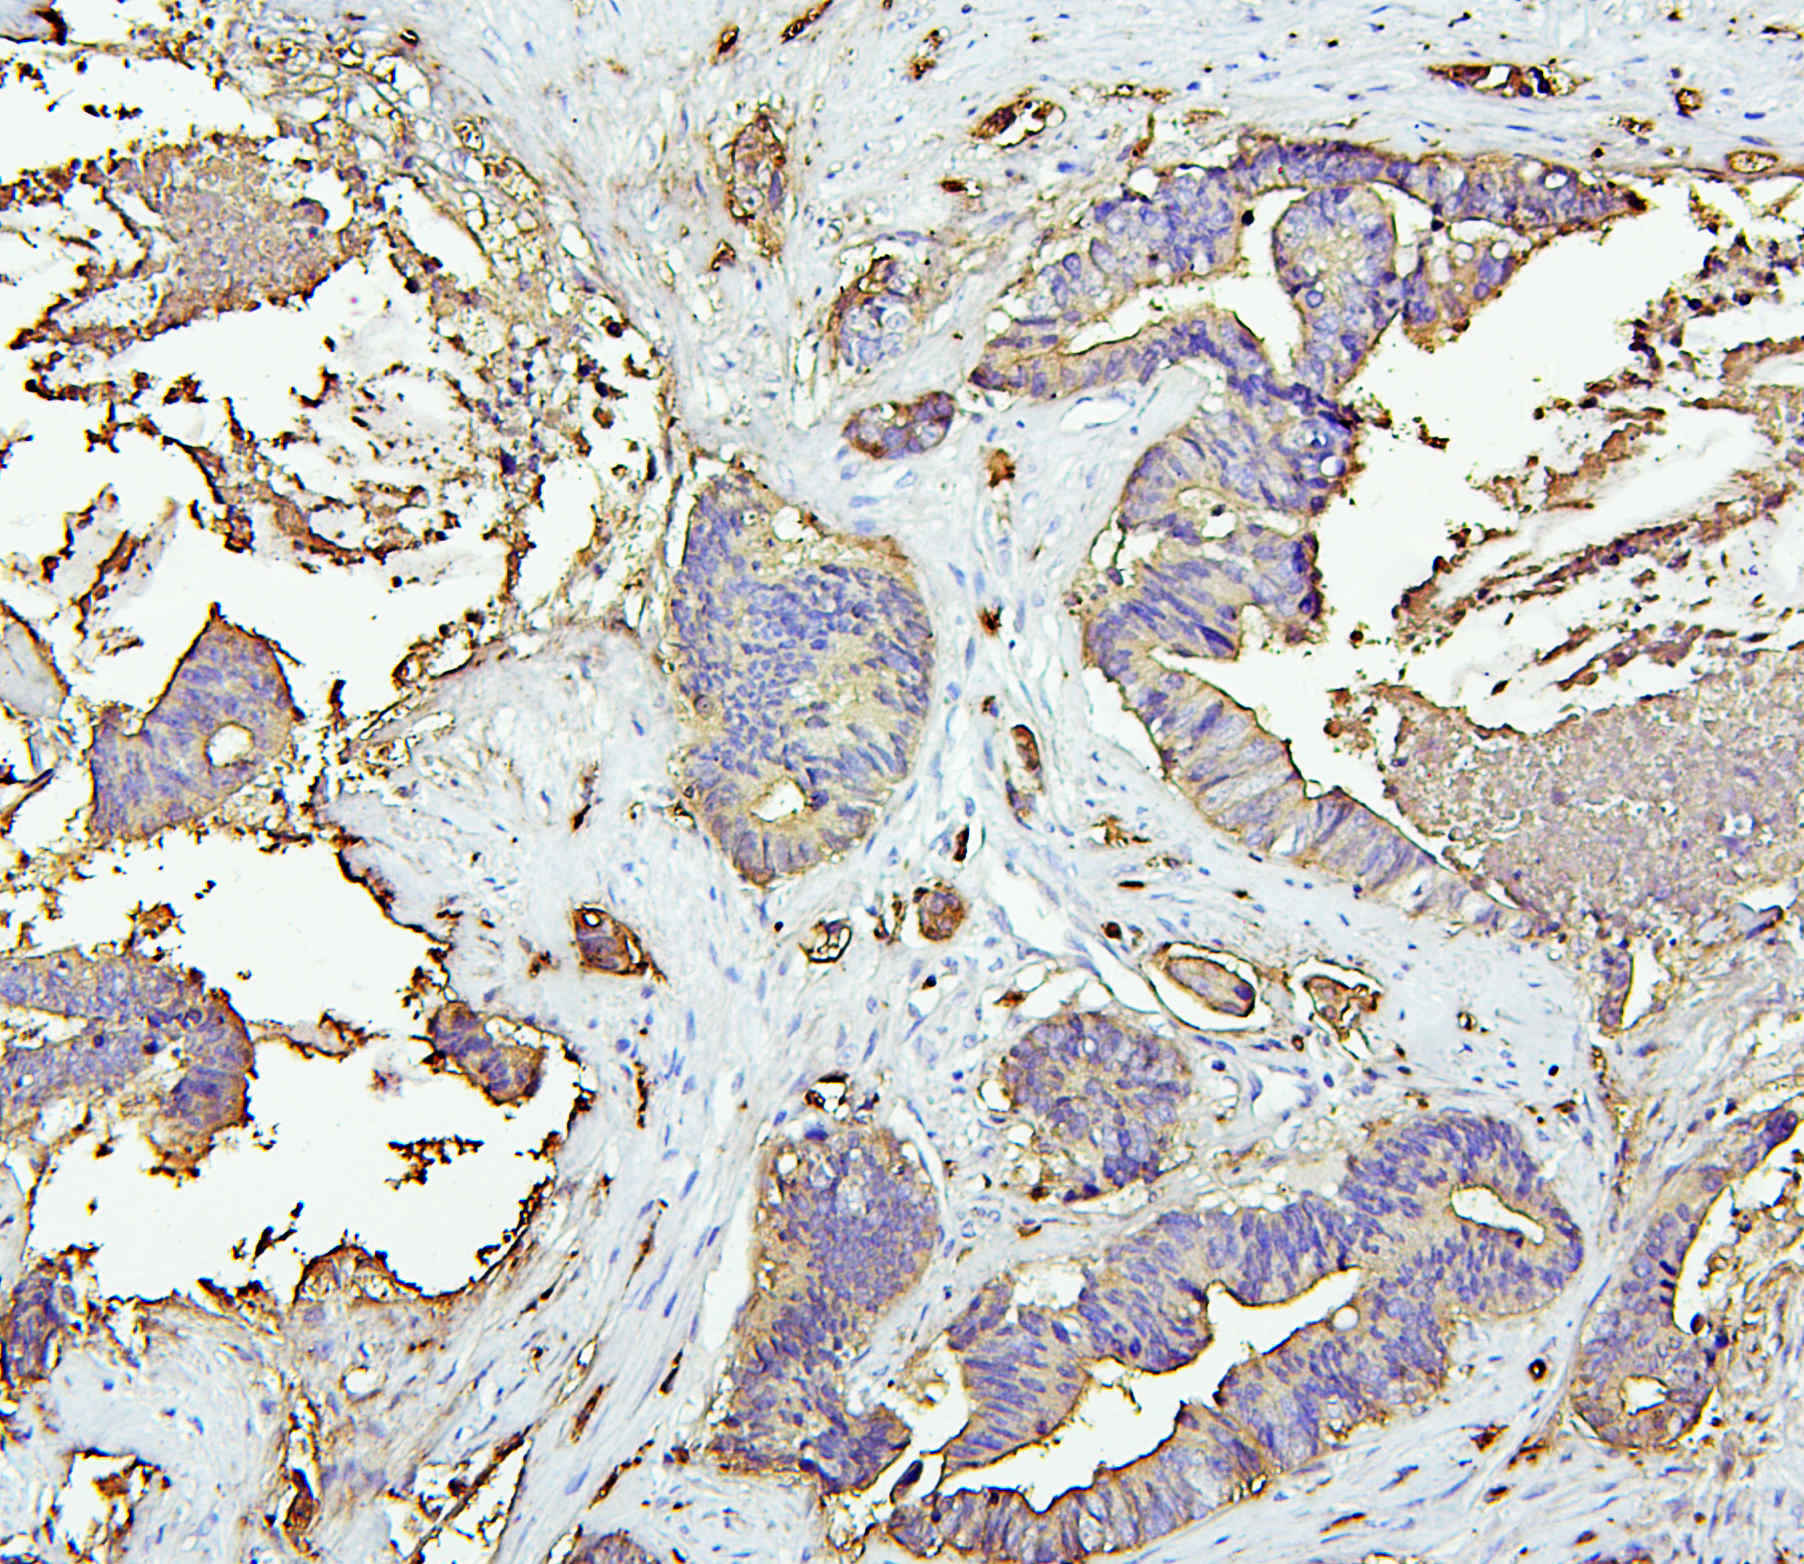

IHC analysis of CEA/CEACAM5 using anti-CEA/CEACAM5 antibody (A00356).

CEA/CEACAM5 was detected in a paraffin-embedded section of human colon cancer tissue. Biotinylated goat anti-rabbit IgG was used as secondary antibody. The tissue section was incubated with rabbit anti-CEA/CEACAM5 Antibody (A00356) at a dilution of 1:200 and developed using Strepavidin-Biotin-Complex (SABC) (Catalog # SA1022) with DAB (Catalog # AR1027) as the chromogen.